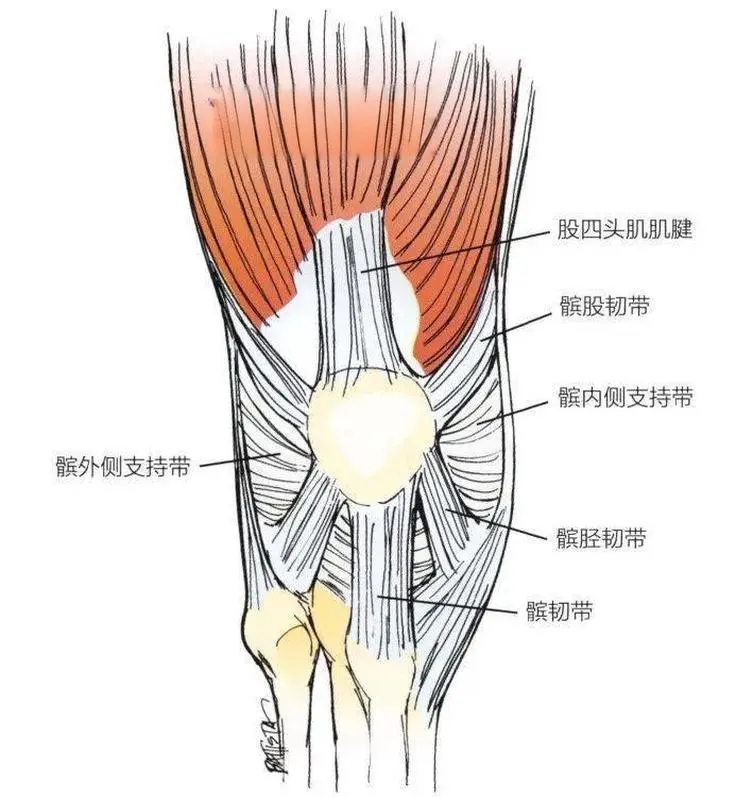

面對小張的疑惑,韋釗嵐主任醫(yī)師解釋,“菠蘿蓋”專業(yè)名稱為髕骨,就是膝關(guān)節(jié)前方突出的圓形的骨頭。髕骨周圍軟組織呈“十字”交叉將髕骨固定在膝關(guān)節(jié)的前方,維持髕骨的穩(wěn)定。

為了幫助小張緩解運(yùn)動時(shí)膝蓋的疼痛,讓她能夠早日重拾自己的街舞愛好,韋釗嵐及科室團(tuán)隊(duì)為小張制定了手術(shù)方案:膝關(guān)節(jié)鏡下微創(chuàng)行內(nèi)側(cè)髕股韌帶的重建+外側(cè)支持帶松解術(shù)。